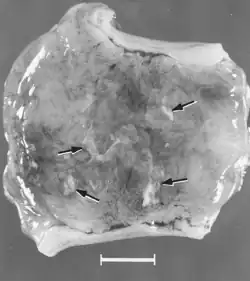

Macroscopic changes of embryos are death followed by resorption of fluids (Fig. 4) and then soft tissues (Fig. 5). Virus and viral antigen are widely distributed in tissues of infected embryos and their placentas,[84] and it is probable that microscopic lesions of necrosis and vascular damage, subsequently described for fetuses, also develop in advanced embryos.

There are numerous macroscopic changes in fetuses infected before they become immunocompetent (Fig. 6). These include a variable degree of stunting and sometimes an obvious loss of condition before other external changes are apparent; occasionally, an increased prominence of blood vessels over the surface of the fetus due to congestion and leakage of blood into contiguous tissues; congestion, edema, and hemorrhage with accumulation of serosanguineous fluids in body cavities; hemorrhagic discoloration becoming progressively darker after death; and dehydration (mummification). Many of these changes also apply to the placenta. Microscopic lesions consist primarily of extensive cellular necrosis in a wide variety of tissues and organs[95][98] (Fig. 7A). Inflammation[98] and intranuclear inclusions[95] also have been described.

Figure 4. Embryos from a gilt experimentally infected oronasally immediately after breeding and killed 22 days later. Bar = 1 cm. (Top) Noninfected, clinically normal embryo (arrow) and associated extraembryonic membranes; (bottom) PPV-infected, dead littermate embryo (arrow) and associated extraembryonic membranes, recent death, no obvious resorption of soft tissues.[84]

Figure 5. Segment of uterus opened to show necrotic remnants of a partially resorbed PPV-infected embryo (arrows) and associated extraembryonic membranes of a gilt experimentally infected oronasally immediately after breeding and killed 22 days later; remnants are laden with virus and viral antigen. Bar = 1 cm.[84]